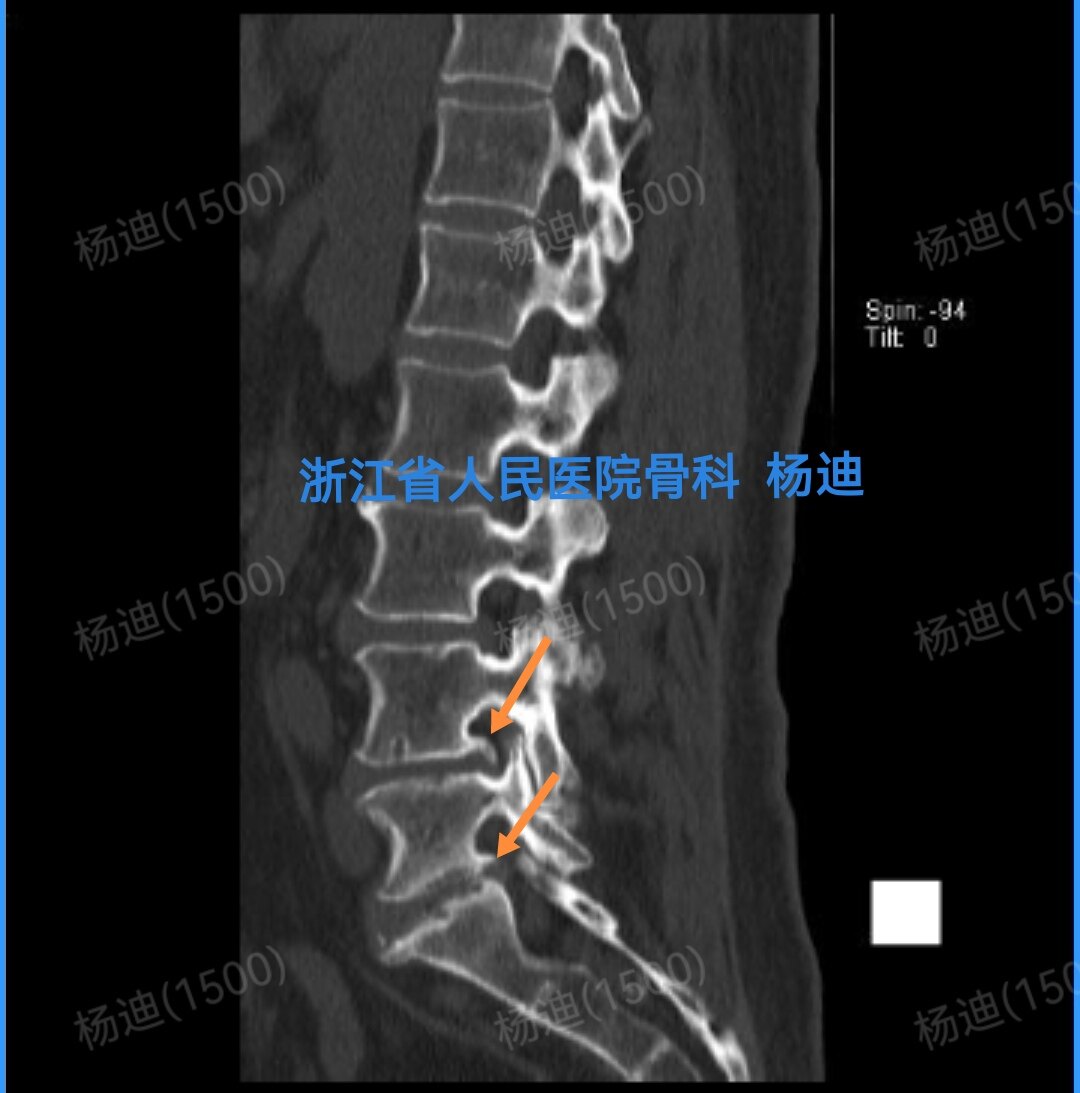

图为CT矢状位重建,提示腰4/5、腰5/骶1椎间盘突出(红色箭头),椎间隙狭窄(橙色直线间距离)。

图为CT矢状位重建,提示腰4/5、腰5/骶1椎间盘突出,后上缘骨赘(橙色箭头)。